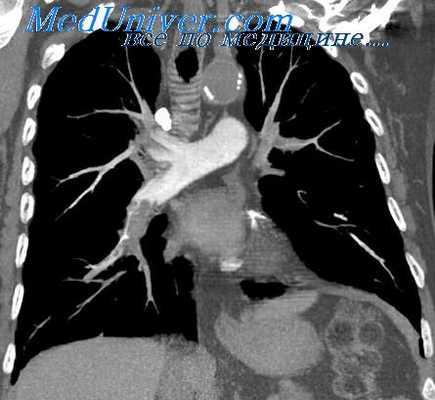

Рис. 1. Общая ангиопульмонография. Контрастное вещество введено катетером. Видны контрастированные сосуды легких. Справа в области ключицы и вдоль позвоночника виден введенный в сердце катетер

Для осуществления общей ангиопульмонографии контрастное вещество в количестве 50—70 мл вводят внутривенно (обычно через локтевую вену) или в полость правого сердца (см. Ангиокардиография) при помощи введенного через вену катетера (рис. 1). При селективной ангиопульмонографии (рис. 2) контрастное вещество вводят в одну из ветвей легочного ствола; для этой цели катетер проводят через правое сердце в легочный ствол и далее в легочную артерию. Для контрастирования одного легкого применяют 20—30 мл контрастного вещества, для исследования одной зоны — 10—15 мл.